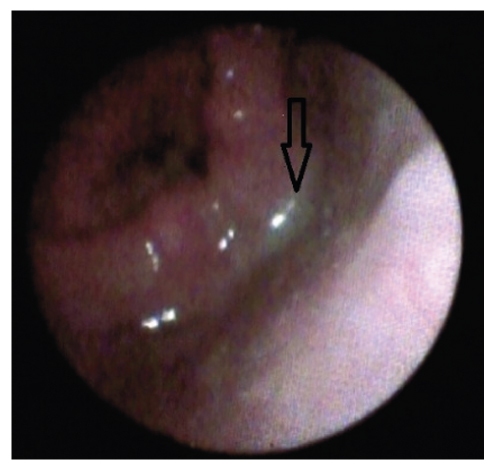

Визуализационная картина фиброоптического эндоскопического исследования с целью определения степени дисфагии отражена на рис. 5, 6.

Рис. 5. Пенетрация с остатками пищи в грушевидных синусах (стрелка) соответствует лёгкой степени дисфагии (2 балла по шкале PAS, 2 балла по шкале FEDSS).